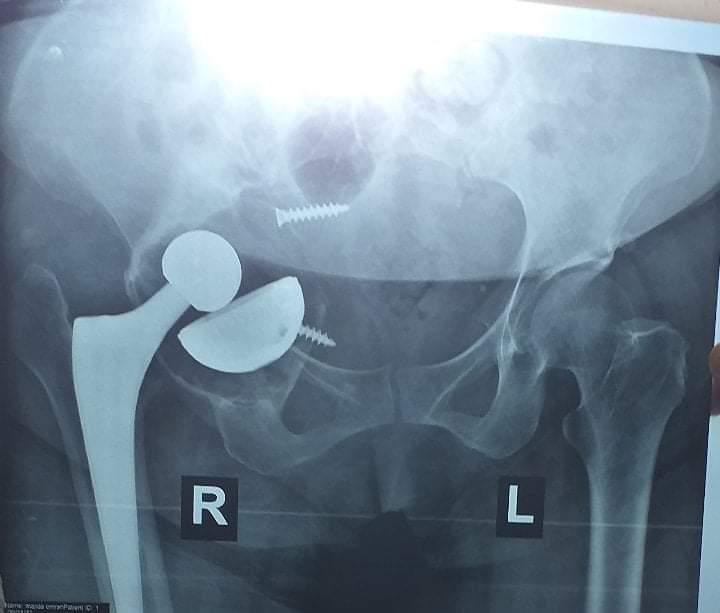

Revision Total Hip Arthroplasty

• Revision Total Hip Arthroplasty